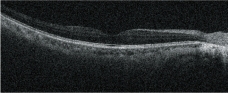

高清追蹤plus功能

高清追蹤plus功能可追蹤無意識的眼球運動,在SLO圖像上保持相同的掃描位置,確保精確的圖像采集。此功能可獲得多至120張疊加的高清圖像。